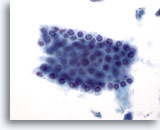

画像 1: 肝FNA – 良性肝細胞 良性肝細胞の小さな集塊。細胞は多角形のものもあれば円形のものもみられ、細胞境界は明瞭です。 核は中心性に位置し、周辺の細胞質は顆粒状を呈しています。細胞質内に色素沈着がみられます。小型の核小体がみられるものの、異型性および高N/C比は認められません。

60倍

画像 1

肝FNA – 良性肝細胞

良性肝細胞の小さな集塊。細胞は多角形のものもあれば円形のものもみられ、細胞境界は明瞭です。 核は中心性に位置し、周辺の細胞質は顆粒状を呈しています。細胞質内に色素沈着がみられます。小型の核小体がみられるものの、異型性および高N/C比は認められません。

60倍